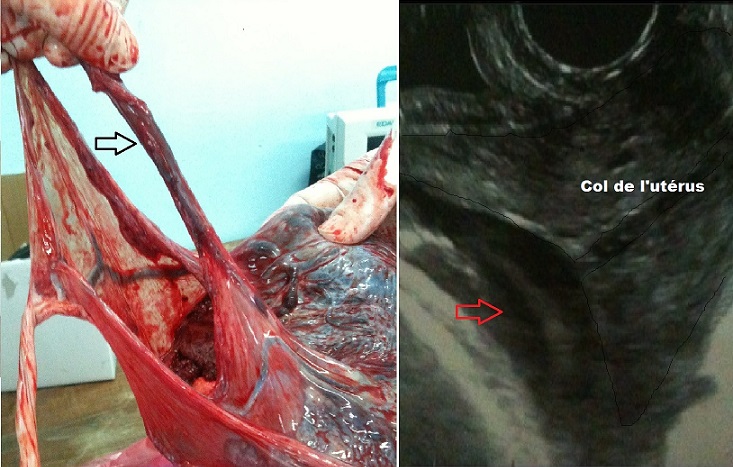

Il s’agit d’une patiente âgée de 36 ans, sans antécédents particuliers, G3P3, ayant accouché à deux reprises par voie basse. Elle a été admise par le biais des urgences à un terme de 38 Semaines d’aménorrhée pour entrée spontanée en travail. Une échographie obstétricale a été pratiquée objectivant un placenta antérieur loin du col et une image oblongue rappelant le cordon ombilical interposée entre la présentation et l’orifice interne du col (Flèche). Le diagnostic de procubitus du cordon a été suspecté et une césarienne en urgence a été décidée. Lors du transfert au bloc opératoire, une rupture spontanée des membranes est survenue. La césarienne s’est déroulée en extrême urgence sous anesthésie générale permettant l’extraction d’un nouveau-né avec un score d’Apgar à 8 à 1 min puis 10 à 5 minutes. L’examen du délivre a objectivé une insertion placentaire antérieure loin du col avec insertion vélamenteuse du cordon et de gros vaisseaux qui partent du point d’insertion du cordon et qui parcourent la surface des membranes (Figure 1).